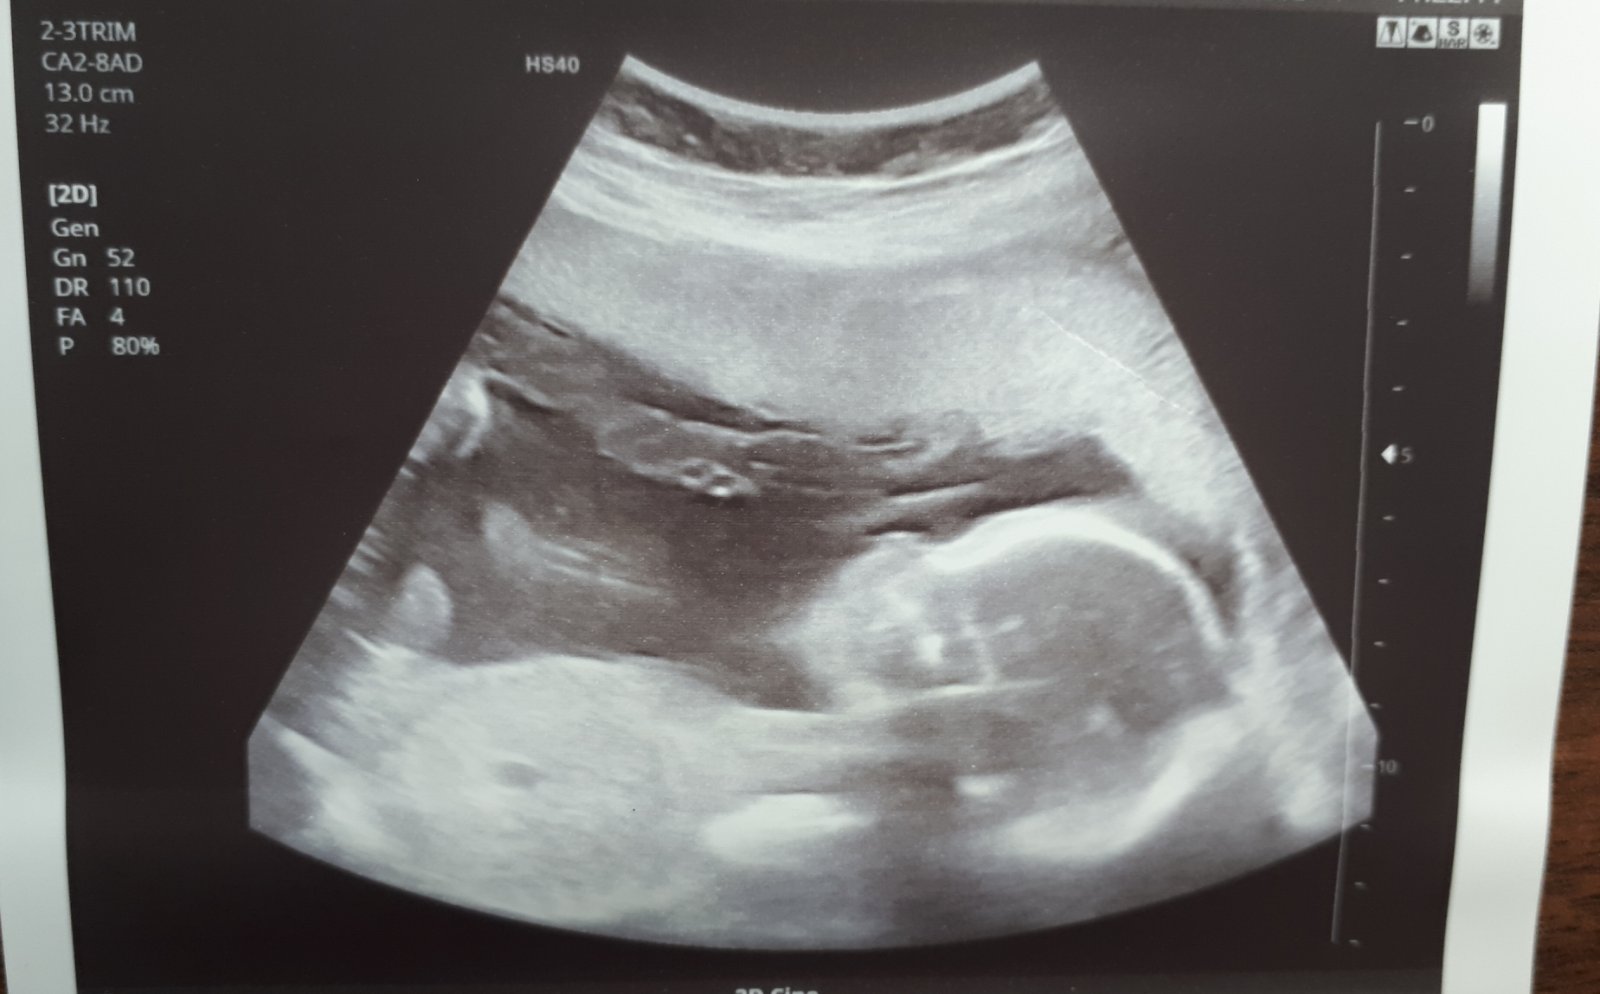

20. 3. 2020

- dnes velký UTZ, mimčo se mrskalo jak blázen, vše je v pořádku, vše změřeno, prohlédnuto a mimi přesně odpovídá 20+4tt - váha mimi 375 g

- moje váha 73 kg, přírůstek +5 kg 😞